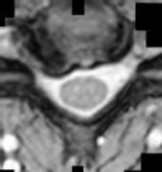

Figures 1 and 2 show sagittal and axial MRI from an 83-year-old woman with an ataxic gait, loss of dexterity, and intermittent loss of bowel and bladder control. The symptoms have been getting progressively worse over the past several weeks.

What disease process is most likely the cause of the patient’s symptoms?

4. Pigmented villonodular synovitis Discussion: B

The patient has a pannus at the C1-2 articulation that is compressing the spinal cord and causing myelopathy symptoms. The development of a pannus at this location has been associated with rheumatoid arthritis. Steinberger and associates showed increased morbidity and mortality when using an anterior approach and the surgery took longer than 4 hours. Chieng and associates showed better outcomes and lower complications rates using a posterior approach.